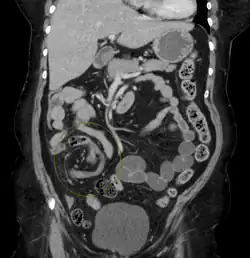

| Coronal CT of the abdomen, demonstrating a volvulus as indicated by twisting of the bowel stock | |

Coronal view of sigmoid volvulus with "whirlpool sign" -